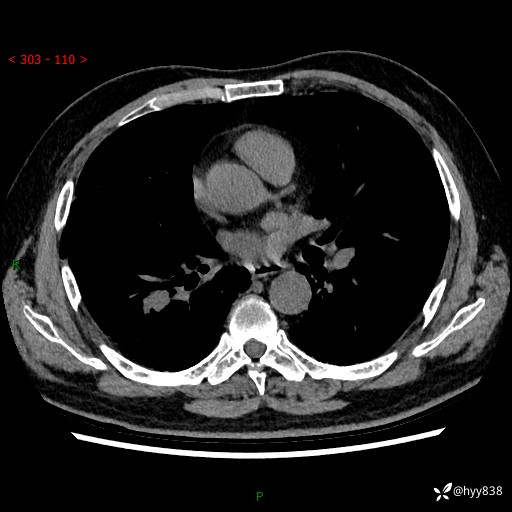

【现病史】:患者半月前无明显诱因出现咳嗽、咳痰,为白色粘痰,无明显加重与缓解因素,伴气促,无发热,无大量脓痰,无胸痛、咯血,无哮鸣音,到我院就诊,胸部CT示右肺结节增大,并口服药物治疗无明显好转,具体用药不详,为求进一步治疗随来我院,经门诊以“孤立性肺结节”收入我科。 病程中患者精神、饮食可,睡眠不佳,大小便正常,体力下降,体重未见明显下降。

【检查】:胸部CT平扫+增强